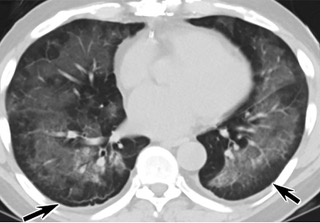

中、下肺軸位CT平掃顯示毛玻璃樣混濁伴胸膜下保留(箭頭)。(同一病人CT影像)

16位被文獻(xiàn)報(bào)道為電子煙肺炎的患者被專家判定為“病毒性感染”,即有可能是新冠肺炎的“疑診患者”,其中更有5位臨床癥狀和治療情況相對完整的患者被判定為“中度可疑”。因此在2019年美國報(bào)道的電子煙肺炎中存在病毒性感染的病例,而且不排除美國電子煙肺炎中存在新冠肺炎的可能性。

疑點(diǎn)三,這16位患者均來自美國,其中4位患者的患病時(shí)間不詳,其余12位的發(fā)病時(shí)間均在2020年以前。針對美國早期新冠病例可能早于已知時(shí)間的報(bào)道和報(bào)告,美方始終沒有回應(yīng)。